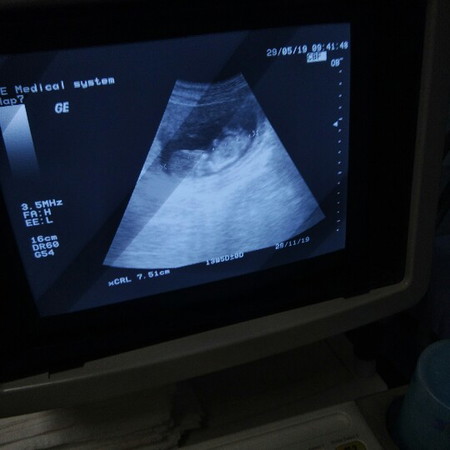

13วีค 5 เดย์ ป่าวค่ะ ในใบซาวเขียน ยาว7เซน และตัวเด็กเหมือนแค่3เดือน ของเรา 4เดือน แขนขายาวแล้ว ยาว14เซน ตัวใหญ่กว่านี้ หรือหมอบอก4เดือนค่ะ